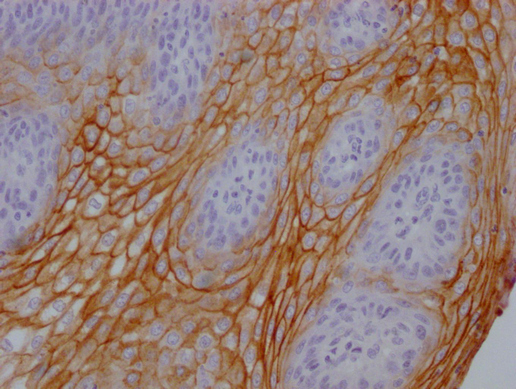

Human skin tissue

1:100